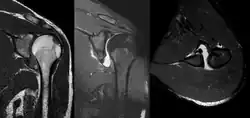

A diagnosis of shoulder dislocation is often suspected based on the person's history and physical examination. Radiographs are made to confirm the diagnosis. Most dislocations are apparent on radiographs showing incongruence of the glenohumeral joint. Posterior dislocations may be hard to detect on standard AP radiographs, but are more readily detected on other views. After reduction, radiographs are usually repeated to confirm successful reduction and to detect bone damage. After repeated shoulder dislocations, an MRI scan may be used to assess soft tissue damage. In regards to recurrent dislocations, the apprehension test (anterior instability) and sulcus sign (inferior instability) are useful methods for determining predisposition to future dislocation.

A Hill–Sachs lesion is an impaction of the head of the humerus left by the glenoid rim during dislocation.[6] Hill-Sachs deformities occur in 35–40% of anterior dislocations. They can be seen on a front-facing X-ray when the arm is in internal rotation.[11] Bankart lesions are disruptions of the glenoid labrum with or without an avulsion of bone fragment.[12]

An anterior dislocation of the shoulder